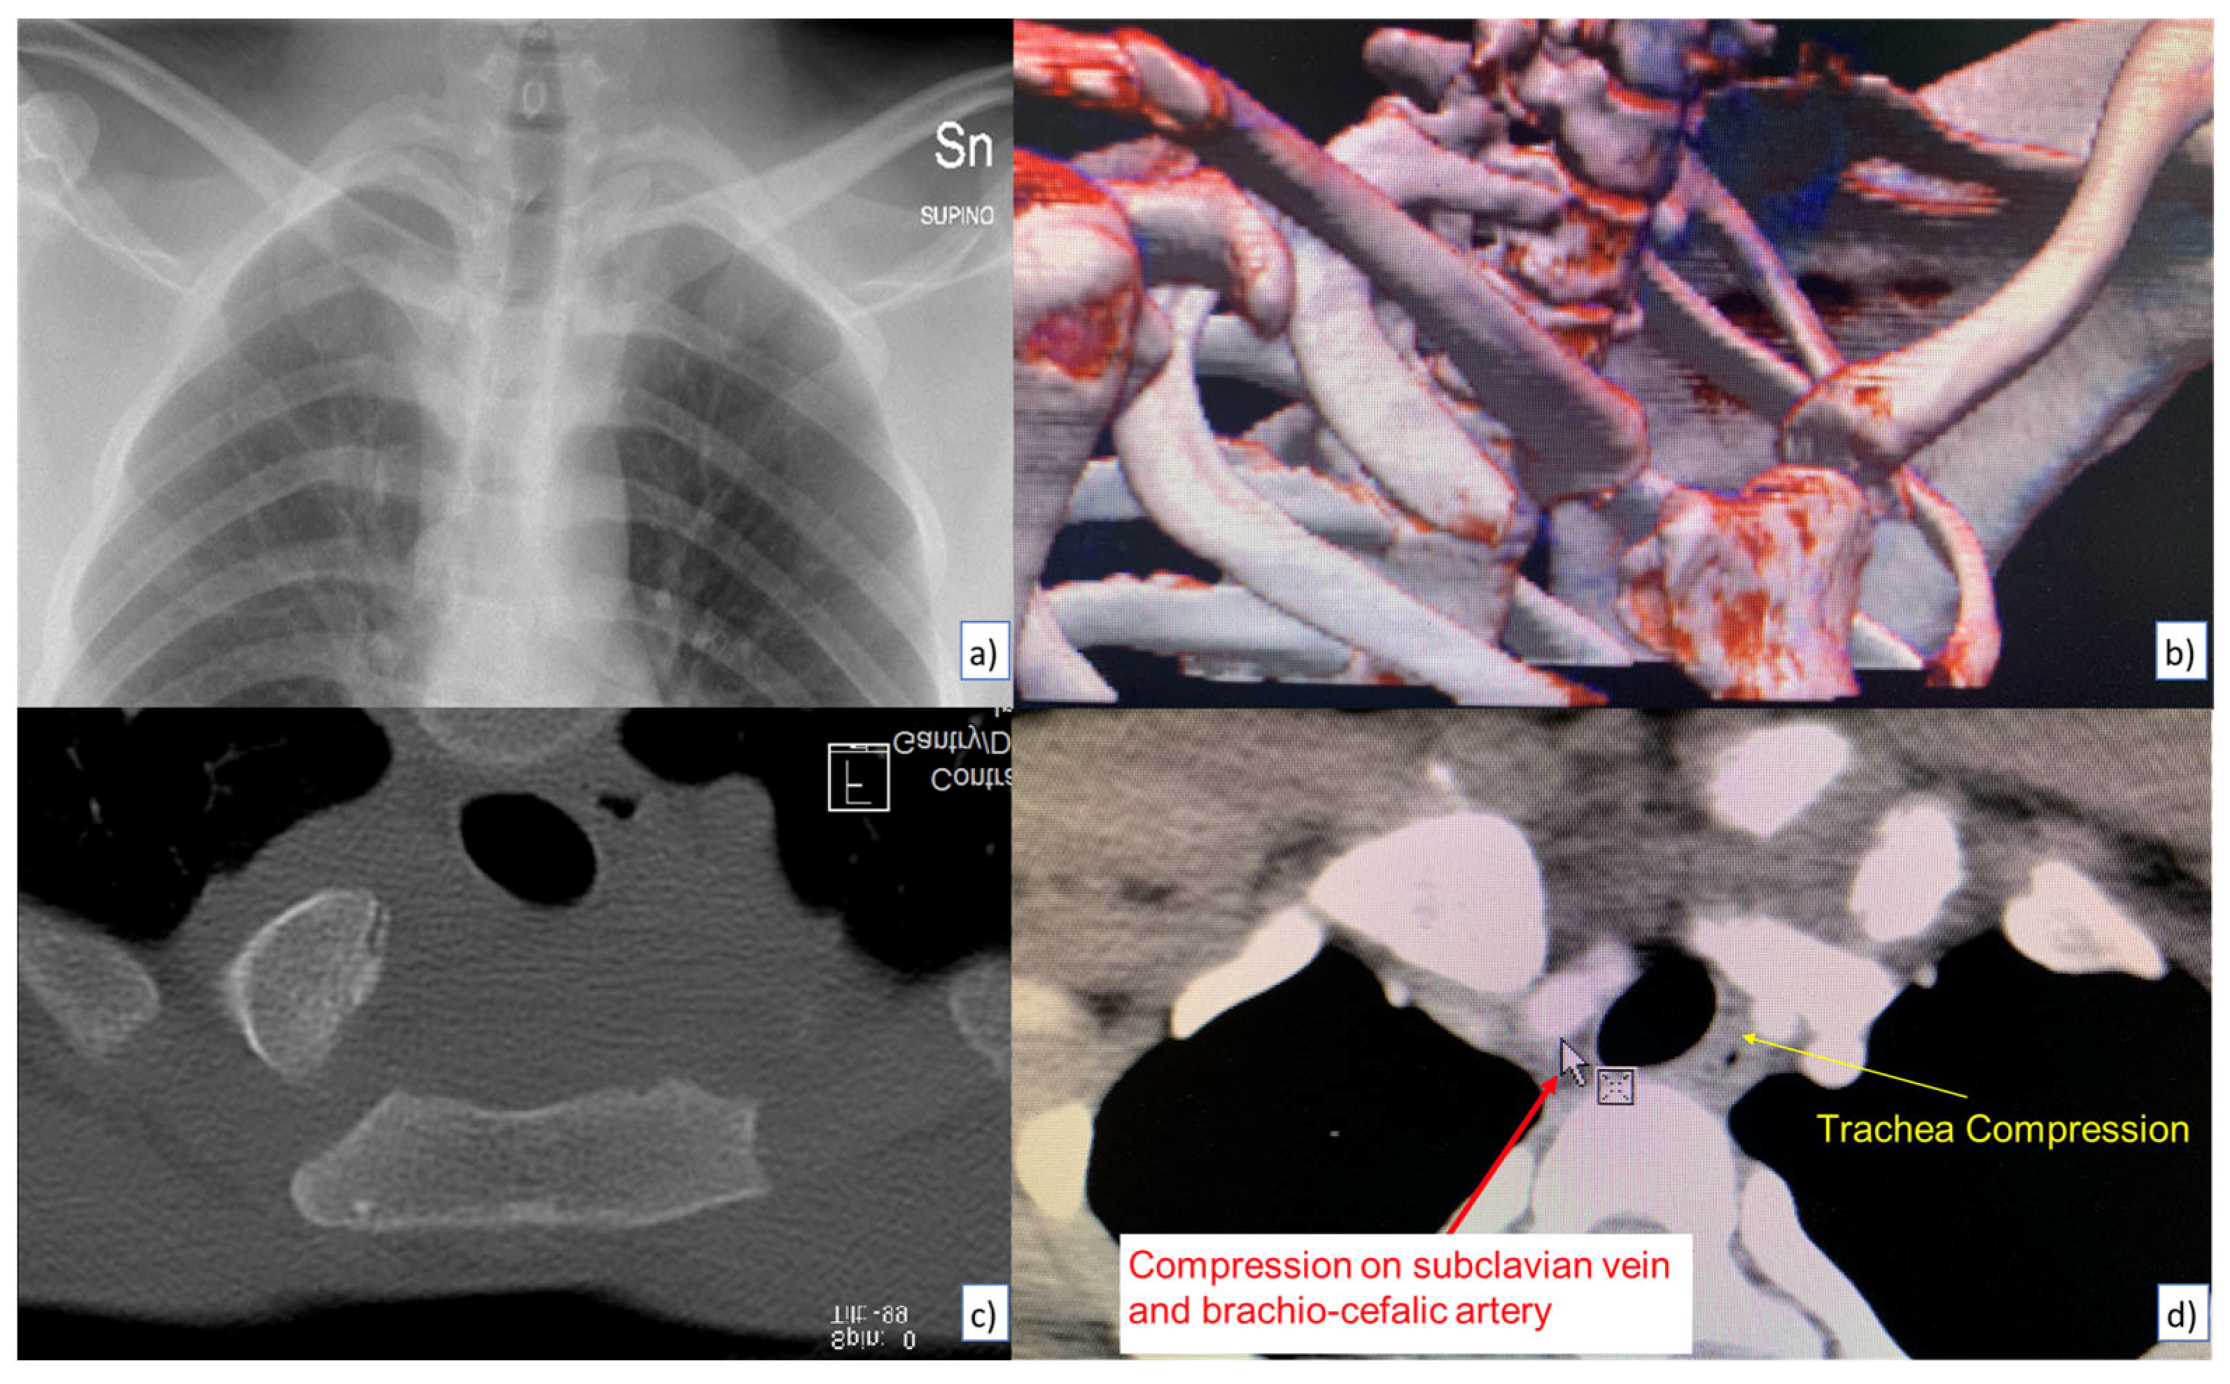

During the whole of 2021, only 2 patients came to our attention after a fall from height. Both of them reported a blow on the postero-lateral side of the shoulder, without loss of consciousness. A full body CT scan was requested for both cases and the medical report was negative for active bleeding, pneumothorax or evidence of internal organs damage; there were instead highlighted fractures and infractions of the ribs, lung parenchymal contusions, apical slight subpleural hematomas and a complete posterior dislocation of the left SCJ (Figure 1). Either way, we tried a closed reduction of the SCJ, which proved fruitless.

Figure 1. Preoperative evaluation: (a) chest x-ray; (b) 3d reconstruction; (c) coronal ct scan; (d) axial CT scan.